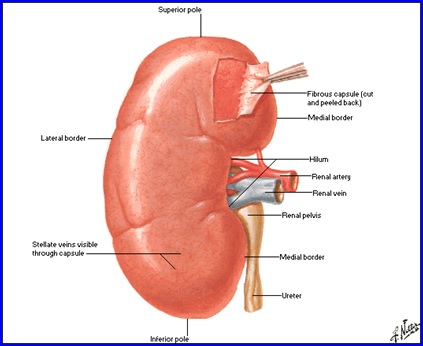

Rinichiul

Organ retroperitoneal, pereche şi simetric, cu formă asemănătoare bobului de fasole.

Dimensiuni şi greutate: depind de statura individului, vârstă, sex şi sunt în medie 12/6/3,5 cm; 140-170g.

Situaţie: de o parte şi alta a coloanei vertebrale, corespunzând vertebrelor T11-T12 superior şi L2-L3 inferior, de-a lungul marginii laterale a m. psoas. Prezenţa ficatului pe partea dreaptă face ca rinichiul drept să fie situat mai jos faţă de cel stâng.

Structură:

- Capsulă fibroasă; grăsime perirenală; fascia renală (Gerota); grăsime paranefretică.

- Sinus renal - elementele pediculului renal.

- Parenchim:

- corticala renală (1,2-1,5 cm grosime; conţine glomerulii renali şi segmente din tubii uriniferi);

- medulara (formată din 8-12 piramide renale).

Sistemul pielo-caliceal

- Calicele minore, în număr de 8-12, drenează fiecare câte o piramidă renală

- Interfaţa dintre piramidă şi calice = paplila renală.

- Calicele minore se unesc pentru a forma 2-3 calice majore care se unesc şi formează bazinetul renal.

- Raporturi anatomice ale bazinetului:

- Intrarenal: ultimul plan al pediculului renal: aretera, vena.

- Extrarenal:

- posterior: m. ilio-psoas;

- anterior dreapta: duodenul 2, vena cava inferioara;

- anterior stganga: corp pancreas.